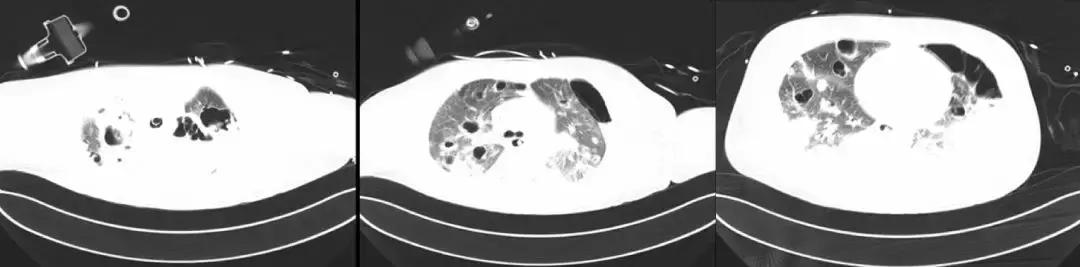

7月27日胸部CT

7月27日成功拔除气切插管;口服利奈唑胺序贯治疗;

8月1日好转出院,转回中心医院继续康复治疗。